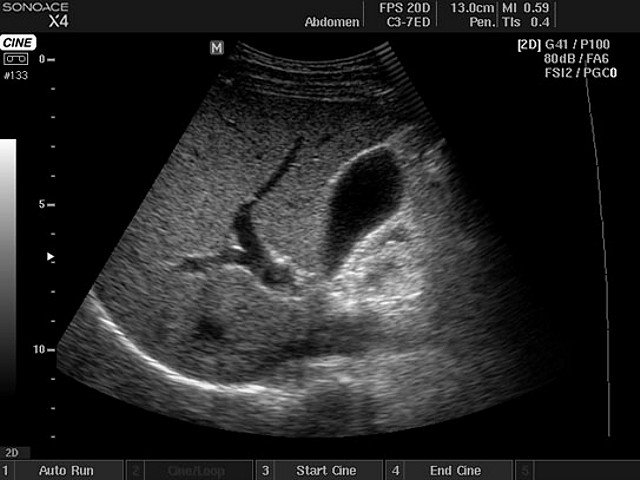

Liver and gallbladder, B-mode (echogramm №401)

Echogramm was received by ultrasound scanner SonoAce-X4 (out of production).